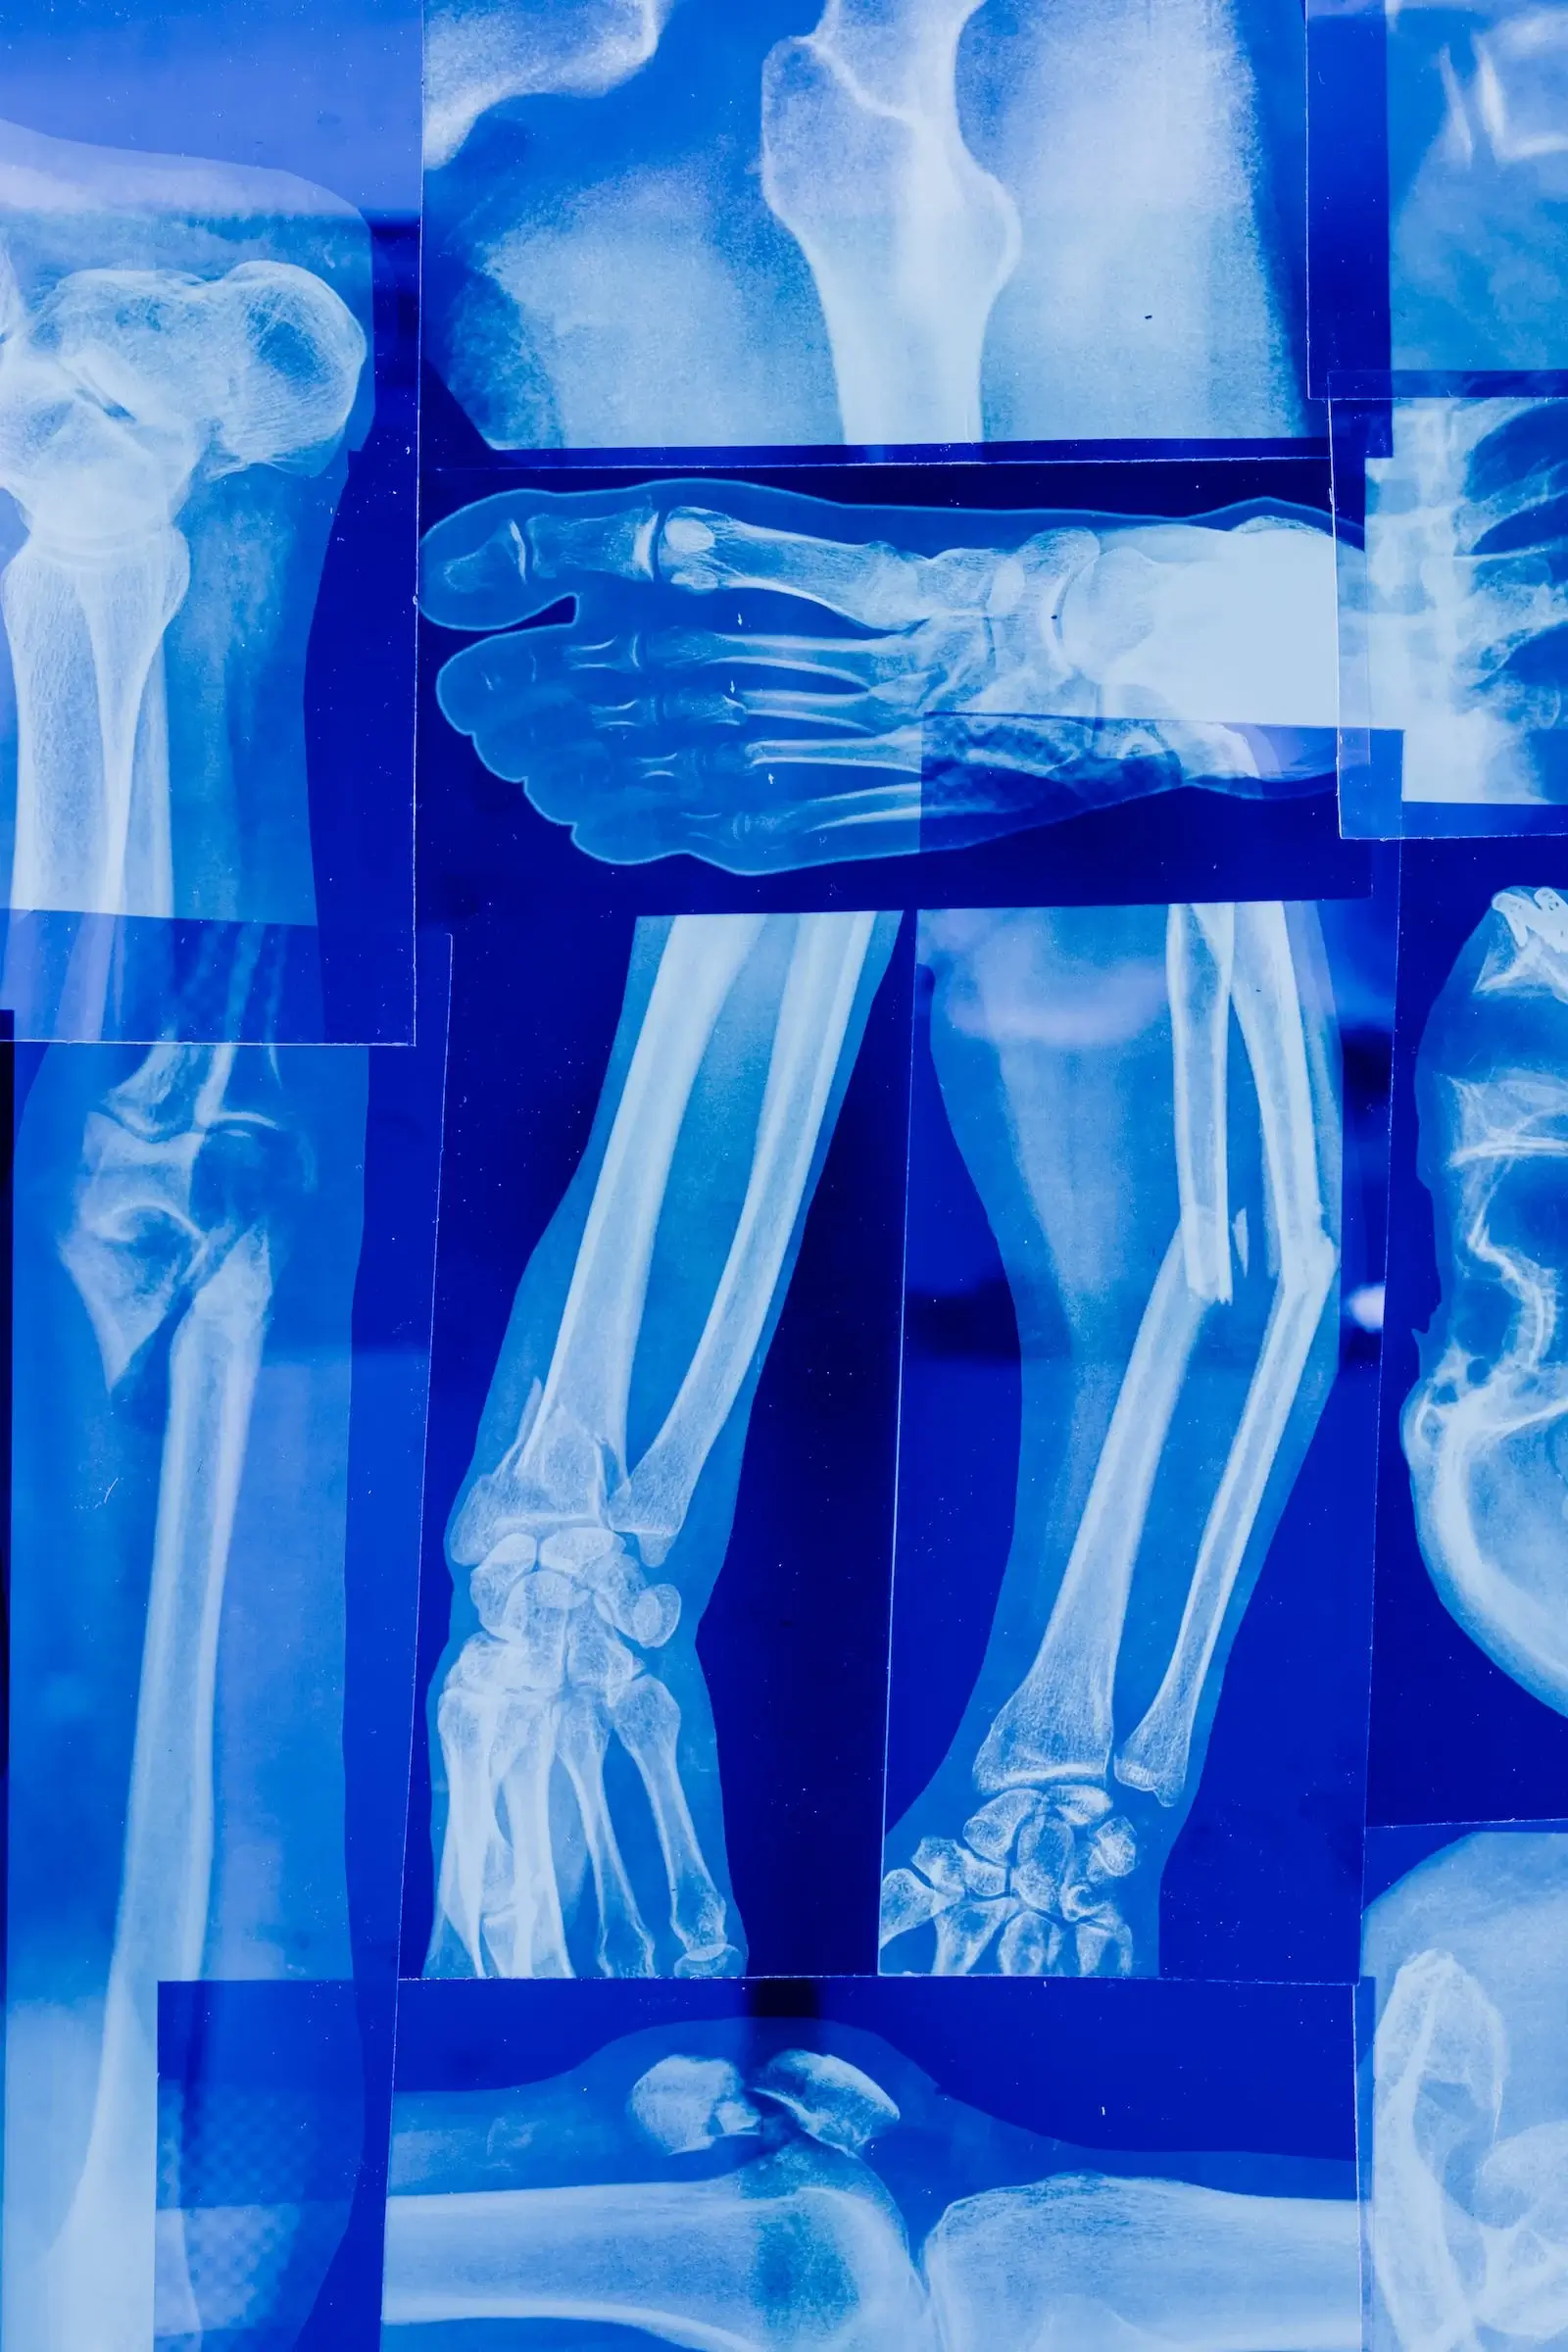

골다공증 원인, 증상, 치료, 예방법_골다공증은 뼈가 쉽게 부러지는 질환으로, 노화, 호르몬 변화, 낮은 칼슘 섭취, 체중 부족, 알코올과 흡연 등이 원인이 됩니다. 조기 발견과 예방이 중요하며, 칼슘 섭취와 규칙적인 운동으로 예방이 가능하며 약물 치료나 보조 기구 사용 등으로 치료가 가능합니다.

골다공증은 뼈의 밀도가 감소하여 뼈가 쉽게 골절되는 질환입니다. 골다공증은 남녀노소 누구나 걸릴 수 있는 질환이며, 특히 여성들이 더 많이 걸리는 편입니다. 대개 초기에는 특별한 증상이 나타나지 않아 무증상으로 진행될 수 있습니다. 하지만 골다공증이 심해지면 허리나 등에 급격한 통증이 나타나고, 뼈 골절 (주로 골반, 척추, 손목, 대퇴골 등에서 발생), 몸통의 길이 감소 (허리와 등의 골절로 인해), 체중 감소, 골절 후에는 아프지 않아서 인지를 못할 수도 있습니다. 이같은 증상이 나타나면 골다공증 가능성을 의심하고 즉시 의사를 방문하여 진단받아야 합니다. 치료 방법은 질병의 정도와 환자의 상황에 따라 다양합니다. 첫 번째 약물치료는 골조직의 손상을 억제하고 골밀도를 높이는 효과가 있습니다. 이러한 약물은 뼈를 구성하는 세포의 작용을 억제하거나 증가시켜서 예방하거나 치료하는 데 사용됩니다. 두 번째 비약물 치료는 생활 습관의 개선이나 운동 치료 등을 통해 증상을 개선하는 방법입니다. 비약물 치료의 방법으로는 건강한 식습관과 영양분 섭취, 금연, 건강한 체중 유지, 알코올 섭취량 감소 등이 있습니다. 세 번째 운동 치료는 골다공증 환자의 근력, 유연성, 균형감각 등을 개선하여 뼈 건강을 유지하고 개선하는 방법입니다. 저항 운동, 유산소 운동, 유연성 운동 등의 다양한 방법이 있으며, 전문가의 지도 하에 안전하게 운동을 진행해야 합니다. 네 번째 수술 치료는 심각한 골다공증 환자의 경우 뼈 골절을 예방하기 위해 수술을 시행할 수도 있습니다. 이러한 수술은 골절 위험성이 높은 골 부위를 보강하는 방식으로 이루어지며, 대퇴골 경골 절단술, 척추 수술, 인공 관절 수술 등이 있습니다.